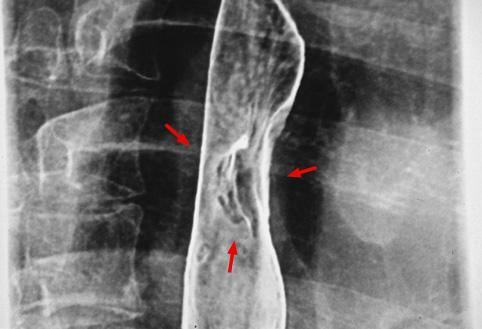

Criteria of Hist.ClassificationMalignant epithelial tumor/Squamous cell carcinoma

LocationEsophagus/Middle third

Technique, MethodX-ray

Macroscopic TypesType 0/IIa (IIa+IIc) Superficial elevated and depressed type

Size15 - 19

Depth of Tumor Invasionsubmucosa